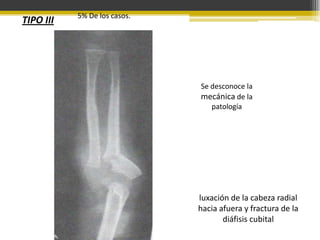

TIPO III

5% De los casos.

Se desconoce la

mecánica de la

patología

luxación de la cabeza radial

hacia afuera y fractura de la

diáfisis cubital